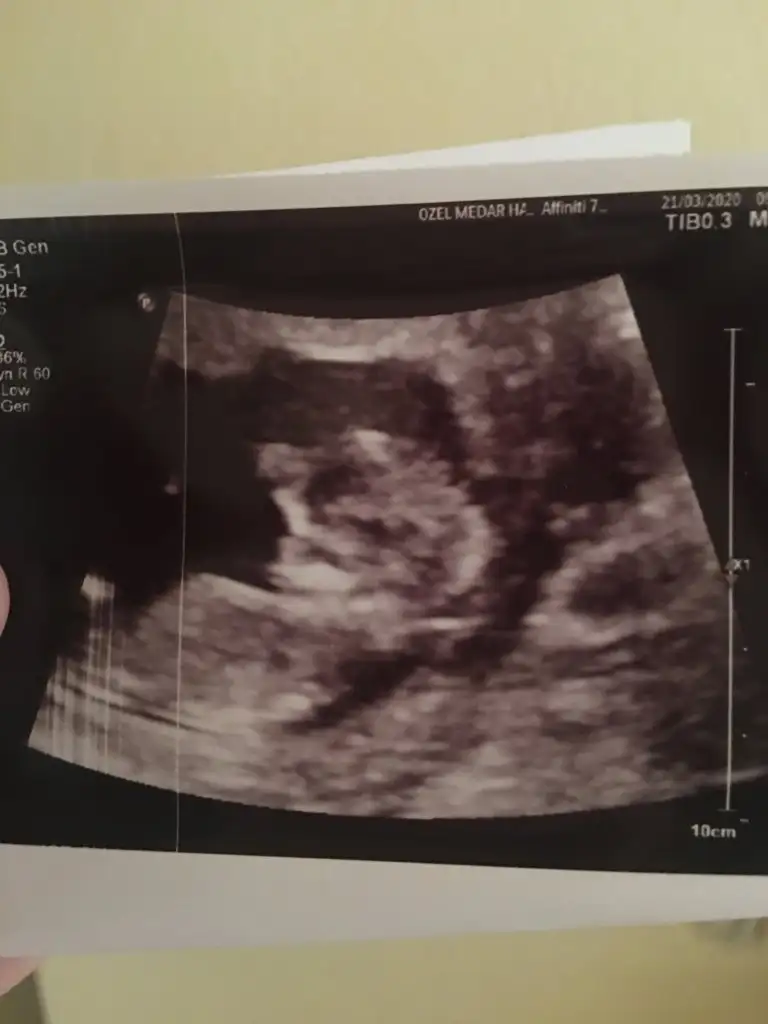

İlk iki foto alttan bakılandan son foto normal daha öncede atmıstım ama cok belli değil demiştiniz bu şekilde bi tahmin olabilirmi Ikra meyra Ikra meyra ☺️

Ikra meyra Ikra meyra keseye göre olan grubu bulamadm buraya atsam yorumlar mısın?